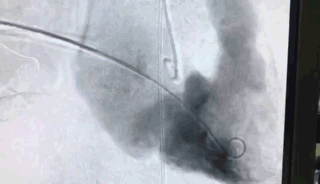

瓣膜植入前右心室造影